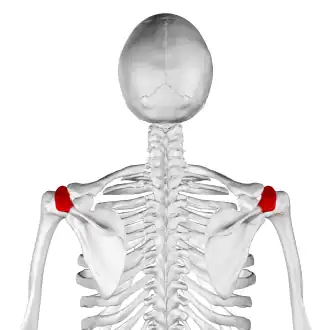

![]() Skeleton, posterior view. Acromion of each scapula shown in red. | |